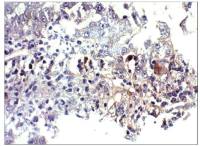

IHC-P analysis of human lymph node tissue using GTX13582 sRANKL antibody [12A668].

Dilution : 5 μg/ml

Antigen retrieval : 10 mM sodium citrate buffer, pH 6.0